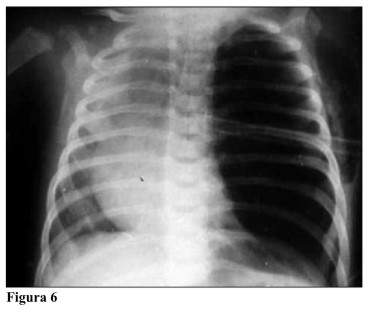

ENFISEMA LOBAR CONGENITO PDF  Congenital lobar emphysema | Radiology Case | Radiopaedia.org

Congenital lobar emphysema | Radiology Case | Radiopaedia.org  Lobar holoprosencephaly | Radiology Case | Radiopaedia.org

Lobar hemorrhage | Radiology Reference Article | Radiopaedia.org  Congenital Lobar Emphysema - The Clinical Advisor

Congenital Lobar Emphysema - The Clinical Advisor  Lobar Holoprosencephaly in 2020 | Retroverted uterus, Cleft lip and palate, Cleft lip

Congenital lobar overinflation | Radiology Reference Article | Radiopaedia.org  CONGENITAL LOBAR EMPHYSEMA | buyxraysonline

CONGENITAL LOBAR EMPHYSEMA | buyxraysonline  ENFISEMA LOBAR CONGENITO PDF

39 Congenital Lobar Emphysema | Radiology Key  Right upper lobe consolidation: an unusual complication of an uneventful endotracheal intubation

Congenital Lobar Emphysema Article  PPT - Chest X-Ray Interpretation for the Internist PowerPoint Presentation - ID:934924

Congenital Lobar Emphysema - Metabolic Disorders - My Fertility Guide  Congenital Lobar Emphysema | Thoracic Key

Congenital Lobar Emphysema | Thoracic Key  a CT showing large lobar hemorrhage at the left parietal lobe. b A | Download Scientific Diagram

Congenital lobar emphysema: diagnostic and therapeutic challenges | BMJ Case Reports  Lobar hemorrhage | MedLink Neurology